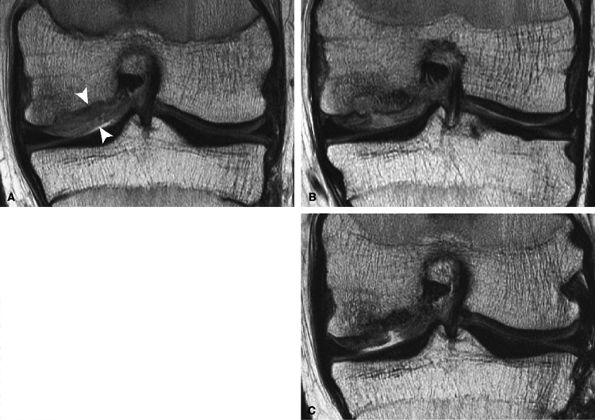

FIGURE 7.23 ● Sagittal inversion recovery (A) and axial fast spin-echo (B) MR images of the knee in a 31-year-old patient obtained 7 weeks following microfracture over the trochlea. Note the hyperintense reparative fibrocartilage over the defect (arrows). Sagittal fast spin-echo MR image (C) also demonstrates basilar delamination of cartilage without flap formation (arrowhead) adjacent to the area of microfracture, over the lateral margin of the trochlea.

|